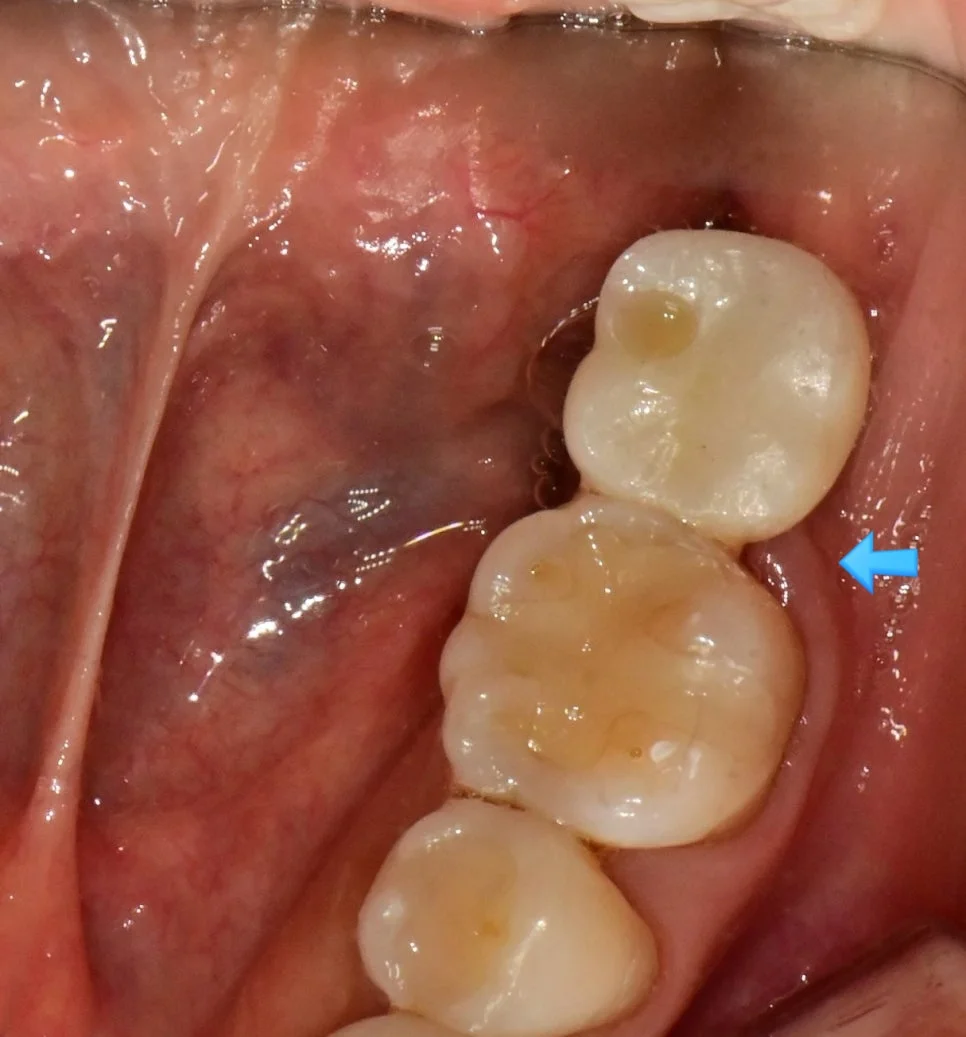

사례 3: 부적합 크라운 교체

왼쪽 위 어금니에 음식물이 많이 낀다는 말씀에 검진을 해보니 잘 맞지 않는 기존 크라운 하방에 상당한 음식물이 저류하고 있는데요.

부적합 기존 크라운 음식물 저류

기존 크라운 하방에 음식물이 고여 있는 상태

잘 맞지 않는 크라운 주변은 음식물이 쉽게 끼고, 그로 인해 냄새까지 발생할 수 있습니다.